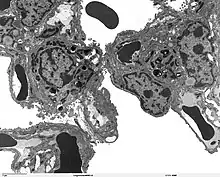

The protein encoded by this gene (SP-A2) is primarily synthesized in lung alveolar type II cells, as part of a complex of lipids and proteins known as pulmonary surfactant. The function of this complex is to reduce surface tension in the alveolus and prevent collapse during expiration. The protein component of surfactant helps in the modulation of the innate immune response, and inflammatory processes.[5]

Alveolar sac region of the lung - TEM

SP-A2 is a member of a subfamily of C-type lectins called collectins. Together with (surfactant protein A1 ) SP-A1, they are the most abundant proteins of pulmonary surfactant. SP-A2 binds to the carbohydrates found in the surface of several microorganisms and helps in the defense against respiratory pathogens.[6][7][8]